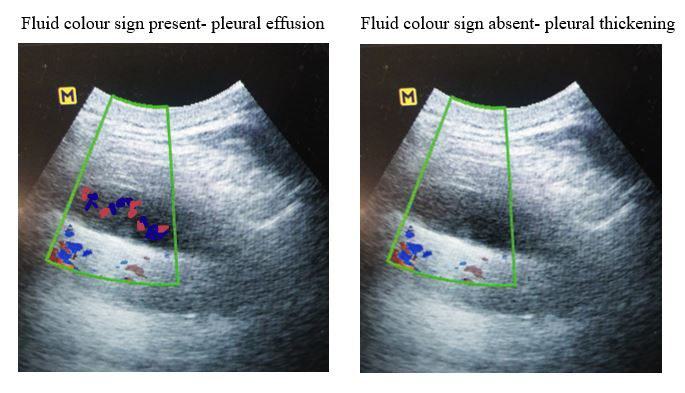

A. Presence of fluid colour sign, pleural effusion.

B. Absent fluid colour sign, pleural thickening.